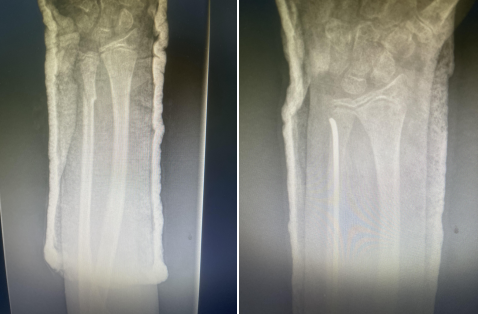

弹性髓内钉技术的特点:

①闭合整复骨折;

②保护了骨折周围的软组织附着和血运,骨折愈合快;

③利用其弹性和双“C”形的固定模式形成髓内支架,骨干周围的肌肉构成软组织框架,达到相对稳定的生物学固定;

④不损伤长骨干两端的骺板;

⑤住院时间短,利于早期返校复学。

因此,该技术是一种微创、安全、有效、并发症少的内固定方法,适用于儿童长骨干横形、斜形及短螺旋形骨折,对肱骨和股骨近、远端干骺端骨折及桡骨颈骨折如应用得当也可获得满意的治疗效果。目前,弹性髓内钉技术在国内外已成为儿童四肢长骨干闭合性骨折治疗的首选方法。

术后应使用石膏或支具固定 6~8,尤其是不稳定性骨折。石膏或支具固定有助于缓解疼痛和减少膝关节周围软组织激惹。当X线片上有连续骨痂出现,可开始部分负重行走。弹性钉取出时间可根据骨折愈合时间及功能恢复情况而定,学龄期儿童寒暑假期间取出内固定为宜。弹性钉留置时间过长,可能会增加取出的难度。股骨干骨折4~5个月可获得坚强愈合;肱骨和胫骨通常需要 3~4 个月;尺桡骨双骨折约 6 个月可获得坚强愈合。而干骺端骨折通常 6~8 周愈合,术后 3 个月即可取出内固定。(骨二科)